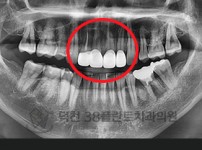

치료전후